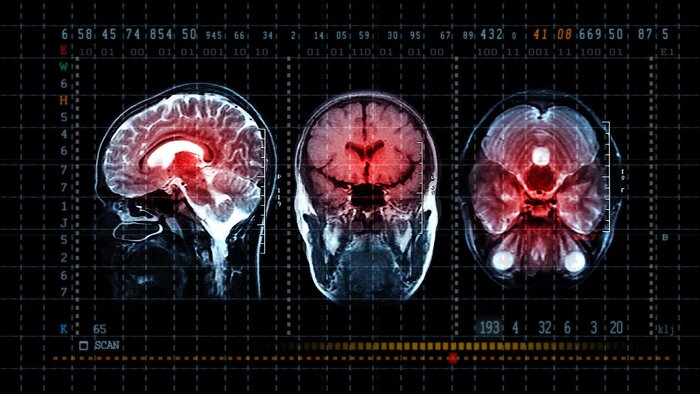

کیوسک خبر: تحقیقات انجام شده در کشور استرالیا نشان داده که یک مدل یادگیری عمیق میتواند به رادیولوژیستها در تفسیر سریعتر و دقیقتر سیتیاسکن مغزی برای تشخیص خونریزی مغزی و نجات جان بیماران یاری برساند.

به گزارش پایگاه خبری انگلیسی «آی نیوز» ، یک مطالعه جدید مشخص کرده است که رادیولوژیستها با استفاده از هوش مصنوعی میتوانند اسکنهای پیچیده مغز را با سرعت و دقت بیشتری ارزیابی کنند .

محققان دریافتند که رادیولوژیستها با کمک هوش مصنوعی میتوانند سیتی اسکن مغز برای خونریزی مغزی را ۳۲ درصد دقیقتر و ۱۱ درصد سریعتر تفسیر کنند.

این مطالعه انتشار یافته در «نشریه اروپایی رادیولوژی» بررسی کرد که ۳۰ رادیولوژیست چگونه قادر به ردیابی «یافته های بالینی» از ۲ هزار و ۸۴۸ مورد سیتیاسکن مغزی با و بدون کمک یک سامانه یادگیری عمیق بودند. این سامانه یادگیری عمیق (هوش مصنوعی) را شرکت استرالیایی «آنالیز» (Annalise) که دفاتری هم در انگلستان دارد ، ساخته است.